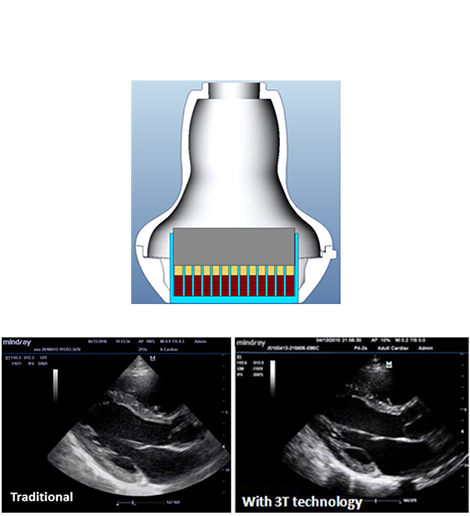

3T Transducer Technology

Mindray’s patent transducer technology to increase image bandwidth and transmission efficiency

- Triple-matching layer design for higher sensitivity, wider bandwidth, and improved S/N.

- Total-cut design for lower cross-talk noise, better directivity, and improved lateral resolution

- Thermal-control design for better acoustic transmission